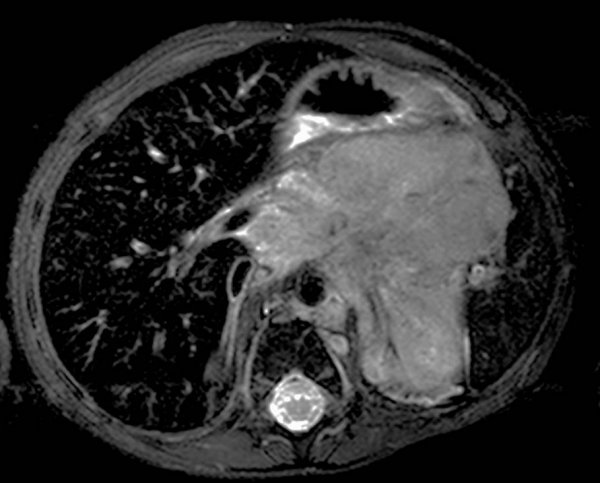

Ultrazvuk trbuha, skener i nuklearna magnetne rezonanca se rutinski koriste prilikom postavljanja dijagnoze.

Neuroblastom predstavlja četvrti po učestalosti malignitet koji se nalazi u pedijatrijskoj populaciji, a ispred njega po učestalosti se nalaze tumori mozga, limfomi i leukemije. U pitanju je najčešći tumor koji se nalazi u trbušnoj duplji kod djece.

U najvećem broju slučajeva, tumori se nalaze u trbušnoj duplji i potiču od nadbubrežnih žlijezda, mada se mogu naći i u drugim tkivima i organima kod svakog petog djeteta, tumor se može naći u grudnom košu u velikom broju slučajeva ne postoje nikakvi simptomi i nalaz je potpuno slučajan.